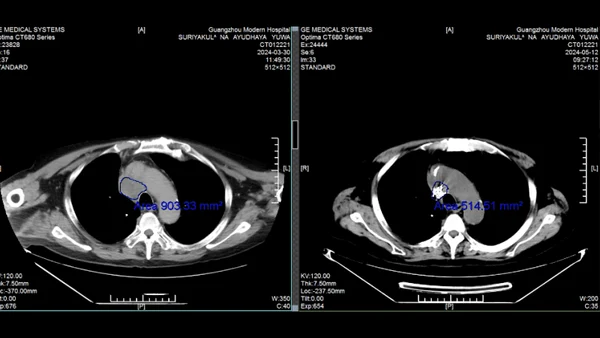

В 2021 году у генерала Ювануда из Таиланда диагностировали рак легких. Несмотря на операцию и курсы химиотерапии, болезнь вернулась с метастазами. Возраст и гипертония сделали дальнейшее традиционное лечение невозможным. К 2023 году состояние ухудшилось: одышка, слабость, необходимость в инвалидном кресле. Семья не сдалась. По рекомендации друга, победившего рак гортани в той же клинике 10 лет назад, генерал обратился в Modern Cancer Hospital Guangzhou.

Мультидисциплинарная команда клиники разработала персонализированный план: 1. Интервенционная терапия - доставка химиопрепаратов непосредственно в опухоль через артерии. 2. Имплантация радиоактивных частиц - точечное уничтожение метастазов. 3. Иммунотерапия - активация собственных защитных сил организма. Результат через 2 курса лечения: • Опухоль уменьшилась на 60%. • Исчезли одышка и необходимость в инвалидном кресле. • Риск синдрома верхней полой вены устранен. «Интервенционная терапия бьет точно в цель, не затрагивая здоровые ткани. Это главное преимущество», - отмечает супруга генерала.